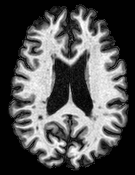

Patch size is another important parameter of the network. In computer vision applications such as object detection, usually a whole 2D image is used as a feature. However, full 3D medical images can not typically be used because of memory limitations. Fig. 4 shows examples of lesion memberships obtained with different sized 2D patches. As the patch sizes increases, the false positives that are mostly observed in the cortex tend to decrease. Fig. 5 shows a plot of Dice and LFPR with various patch sizes, ordered from left to right according to their increasing size. Note that smaller patches ( to ) produced significantly lower Dice and higher LFPR compared to other patches (), as seen from the memberships in Fig. 4. Also some of the highest Dice and lowest LFPR were observed for patches with large in-plane size, i.e., , , and . It was observed in Fig. 5 that there is no significant difference between Dice coefficients for , , or , but LFPR of both and are significantly lower than that of (). We chose as the optimal patch size. Other choices of smaller and patches (not shown) yielded worse results. Note that although training was performed with different patch sizes, the memberships were generated slice by slice, as the trained model consisted only of convolutions and did not need any information about patch sizes.